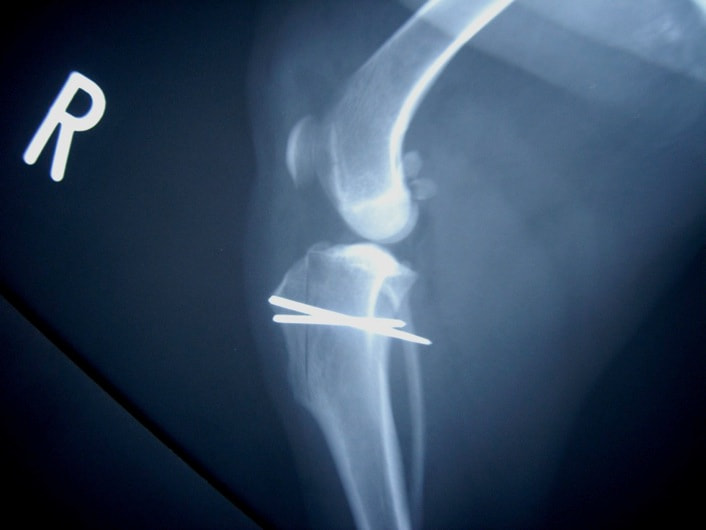

■ 症例20 ポメラニアン 8ヶ月 1.8kg

左右膝蓋骨脱臼 グレードⅢ

2ヶ月前から間欠的跛行が認められ、両膝の膝蓋骨脱臼整復術を行った。

手技は縫工筋及び内側広筋の解放、脛骨粗面の外側転位、滑車ブロック形造溝術、内外側関節包の縫縮を選択し実施した。

右側の膝蓋骨脱臼は上記手技で整復されたものの、左側はそれのみでは膝蓋骨が浮く様子が認められた。その為、PDS縫合糸にて膝蓋靱帯を1糸のみ縫合し、靱帯の縫縮を行った。

膝蓋骨脱臼は膝関節における膝蓋骨の内外側の脱臼と定義されるが、時として単純な内外の脱臼ではなく、膝蓋骨が大きく前方に浮き上がるように脱臼する場合がある。特にトイプードルやポメラニアンといった犬種に多く認められる。

内側脱臼に加えて前方への浮き上がりを矯正する為に、従来より脛骨粗面転移により膝蓋靭帯を外方と下方に引っ張り、固定する方法を選択する。膝蓋骨の前方への浮き上がりが軽度の場合は、従来法ではなく関節包の縫縮で対応していた。しかし、一部の症例で膝蓋骨の動きが悪くなり伸展機構が円滑に機能せずロボット様歩行になるケースがあった。

その為、膝蓋靭帯自体を縫縮する方法を採用した。この方法により、膝関節の伸展機構を妨げず膝蓋骨の軽度の浮きを矯正することが可能となった。

本症例の経過は良好である